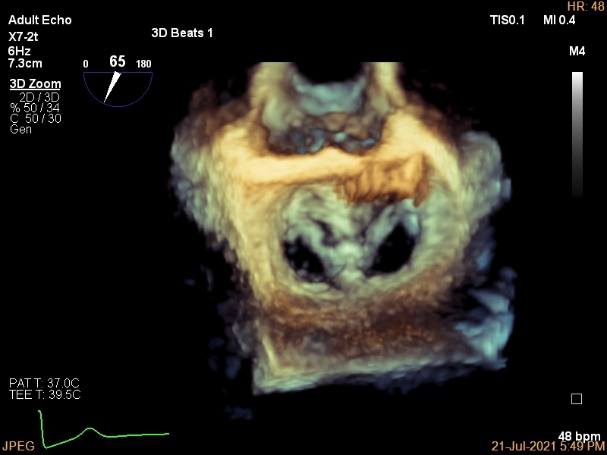

3D MV View

3D-color MV view:血流主要来源于2区近3区

Qlab软件勾画估测瓣口面积约:6.16cm²

3D视图打开夹子

3D视图下调Rotate,定位2区

3D视图下观察二尖瓣双孔形态